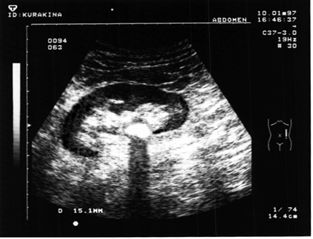

Ультразвуковое исследование позволяет диагностировать такие заболевания, как пиелонефрит, мочекаменная болезнь, гидронефроз, кистозные образования и другие.